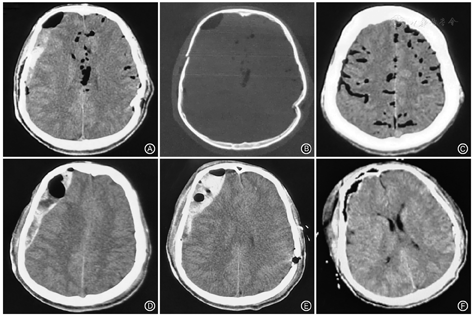

患者男,17岁,因"头面部砸伤后意识不清2 h"入院,患者躁动,难以平卧,头左侧颞枕部创口可触及颅骨凹陷,颜面部多发皮肤裂伤,右侧脑脊液耳漏鼻漏,头右侧无创口,颈强直。门诊镇静治疗后检查头颅CT:左侧颞骨凹陷粉碎骨折、右侧颞骨骨折伴新月形血肿,颅内大量积气,下颌骨骨折、眼眶骨折(图1A~C)。血常规未见贫血及血小板异常,D-二聚体增高,凝血轻度异常。右侧颞骨类似新月形血肿伴积气,诊断为硬膜下血肿,血肿量不多。因左侧颞骨凹陷深度达2.0 cm伴创口,予以当日急诊凹陷骨折整复、伤口清创缝合术。次日术后复查CT见颅内积气减少,左侧颞骨凹陷整复,术区无迟发血肿。但右侧颅板下血肿及积气增多,形状似同双梭形(图1D、图1E)。因血肿量较多,故于左侧骨折整复术后16 h手术,予以清除右侧血肿。术中见血肿位于硬膜外,硬膜下无血肿,仅见局部少许硬膜下积液,压力较高,释出后压力缓解,探查硬膜完整。术后复查CT见血肿消失,积气消失(图F)。病程中严密监测患者生命体征,给予止血、抗感染及维持水电解质平衡等对症治疗,预防并发症。术后脑脊液耳漏消失,脑脊液鼻漏3 d后消失。抗炎治疗1周,卧床治疗3周后患者意识清楚,无肢体及精神等方面神经功能障碍,治愈出院。

硬膜外和硬膜下积气鉴别方法:硬膜下积气CT表现为颅内蛛网膜下腔散在多发低密度影,硬膜下血肿为新月形[1]。因硬膜与颅骨贴合紧密,硬膜外罕见气体进入,伴有积气的血肿多考虑硬膜下。本例患者伤后初期CT血肿呈类似新月形,伴有颅内积气。且积气与血肿混合存在,对侧凹陷骨折,给人第一印象考虑对冲伤引起硬膜下血肿伴颅内积气。但复查血肿增多时为双凸透镜形,同时积气增多,因合并同部位颞骨骨折,硬膜下还是硬膜外一时难以判断,术中证实为硬膜外血肿并大量积气。临床鉴别可以依靠MRI识别硬膜位置加以区分,但临床医师处理外伤躁动患者较少使用,仍以CT下积气及血肿的表现来鉴别,血肿边缘为梭形考虑硬膜外积气,血肿边缘为新月形时考虑硬膜下积气。